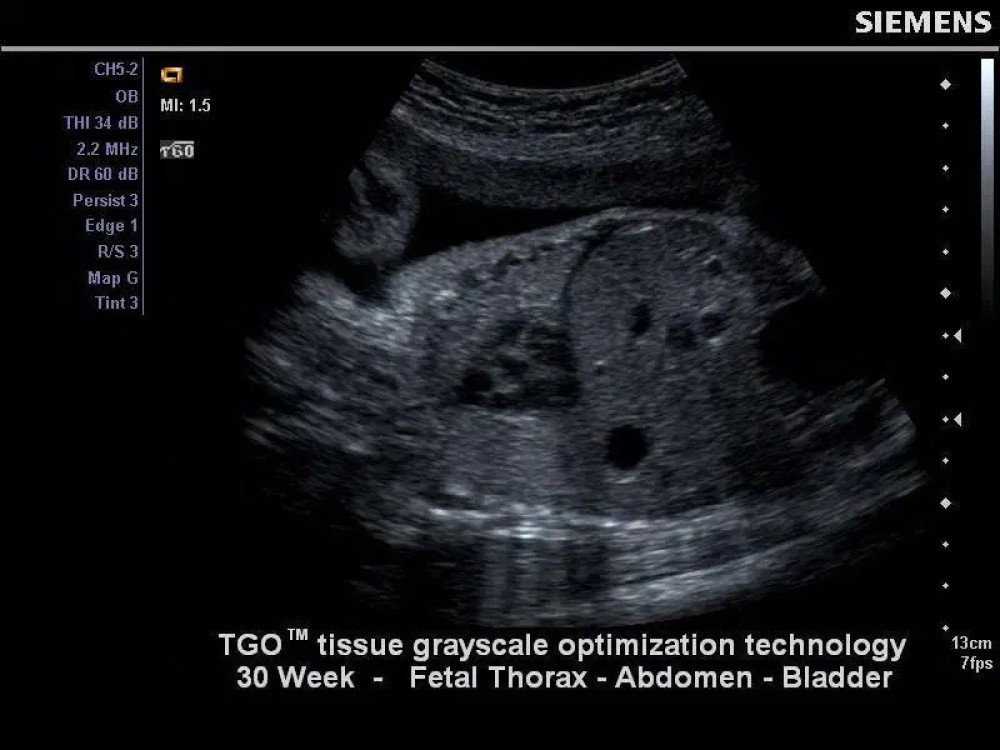

Tissue Grayscale Optimization (TGO): Görüntü parıltısı və qazancını avtomatik tənzimləyərək optimal vizualizasiya təmin edir.

CH5-2 Curved Array Probe

Tezlik: 1.4–5.0 MHz

Tətbiqlər: Obstetriya, Ginekologiya, Abdominal, Böyrək, Pelvik

Elementlər: 128

Uyğunluq: X150, X300, NX2, NX3, NX3 Elite, X600